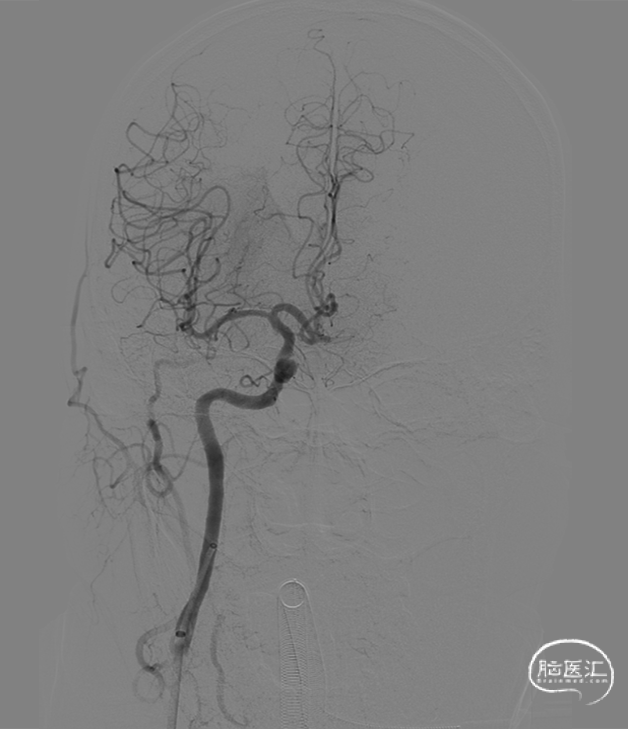

➢ 术后影像

术后造影。

术后1周CTA。